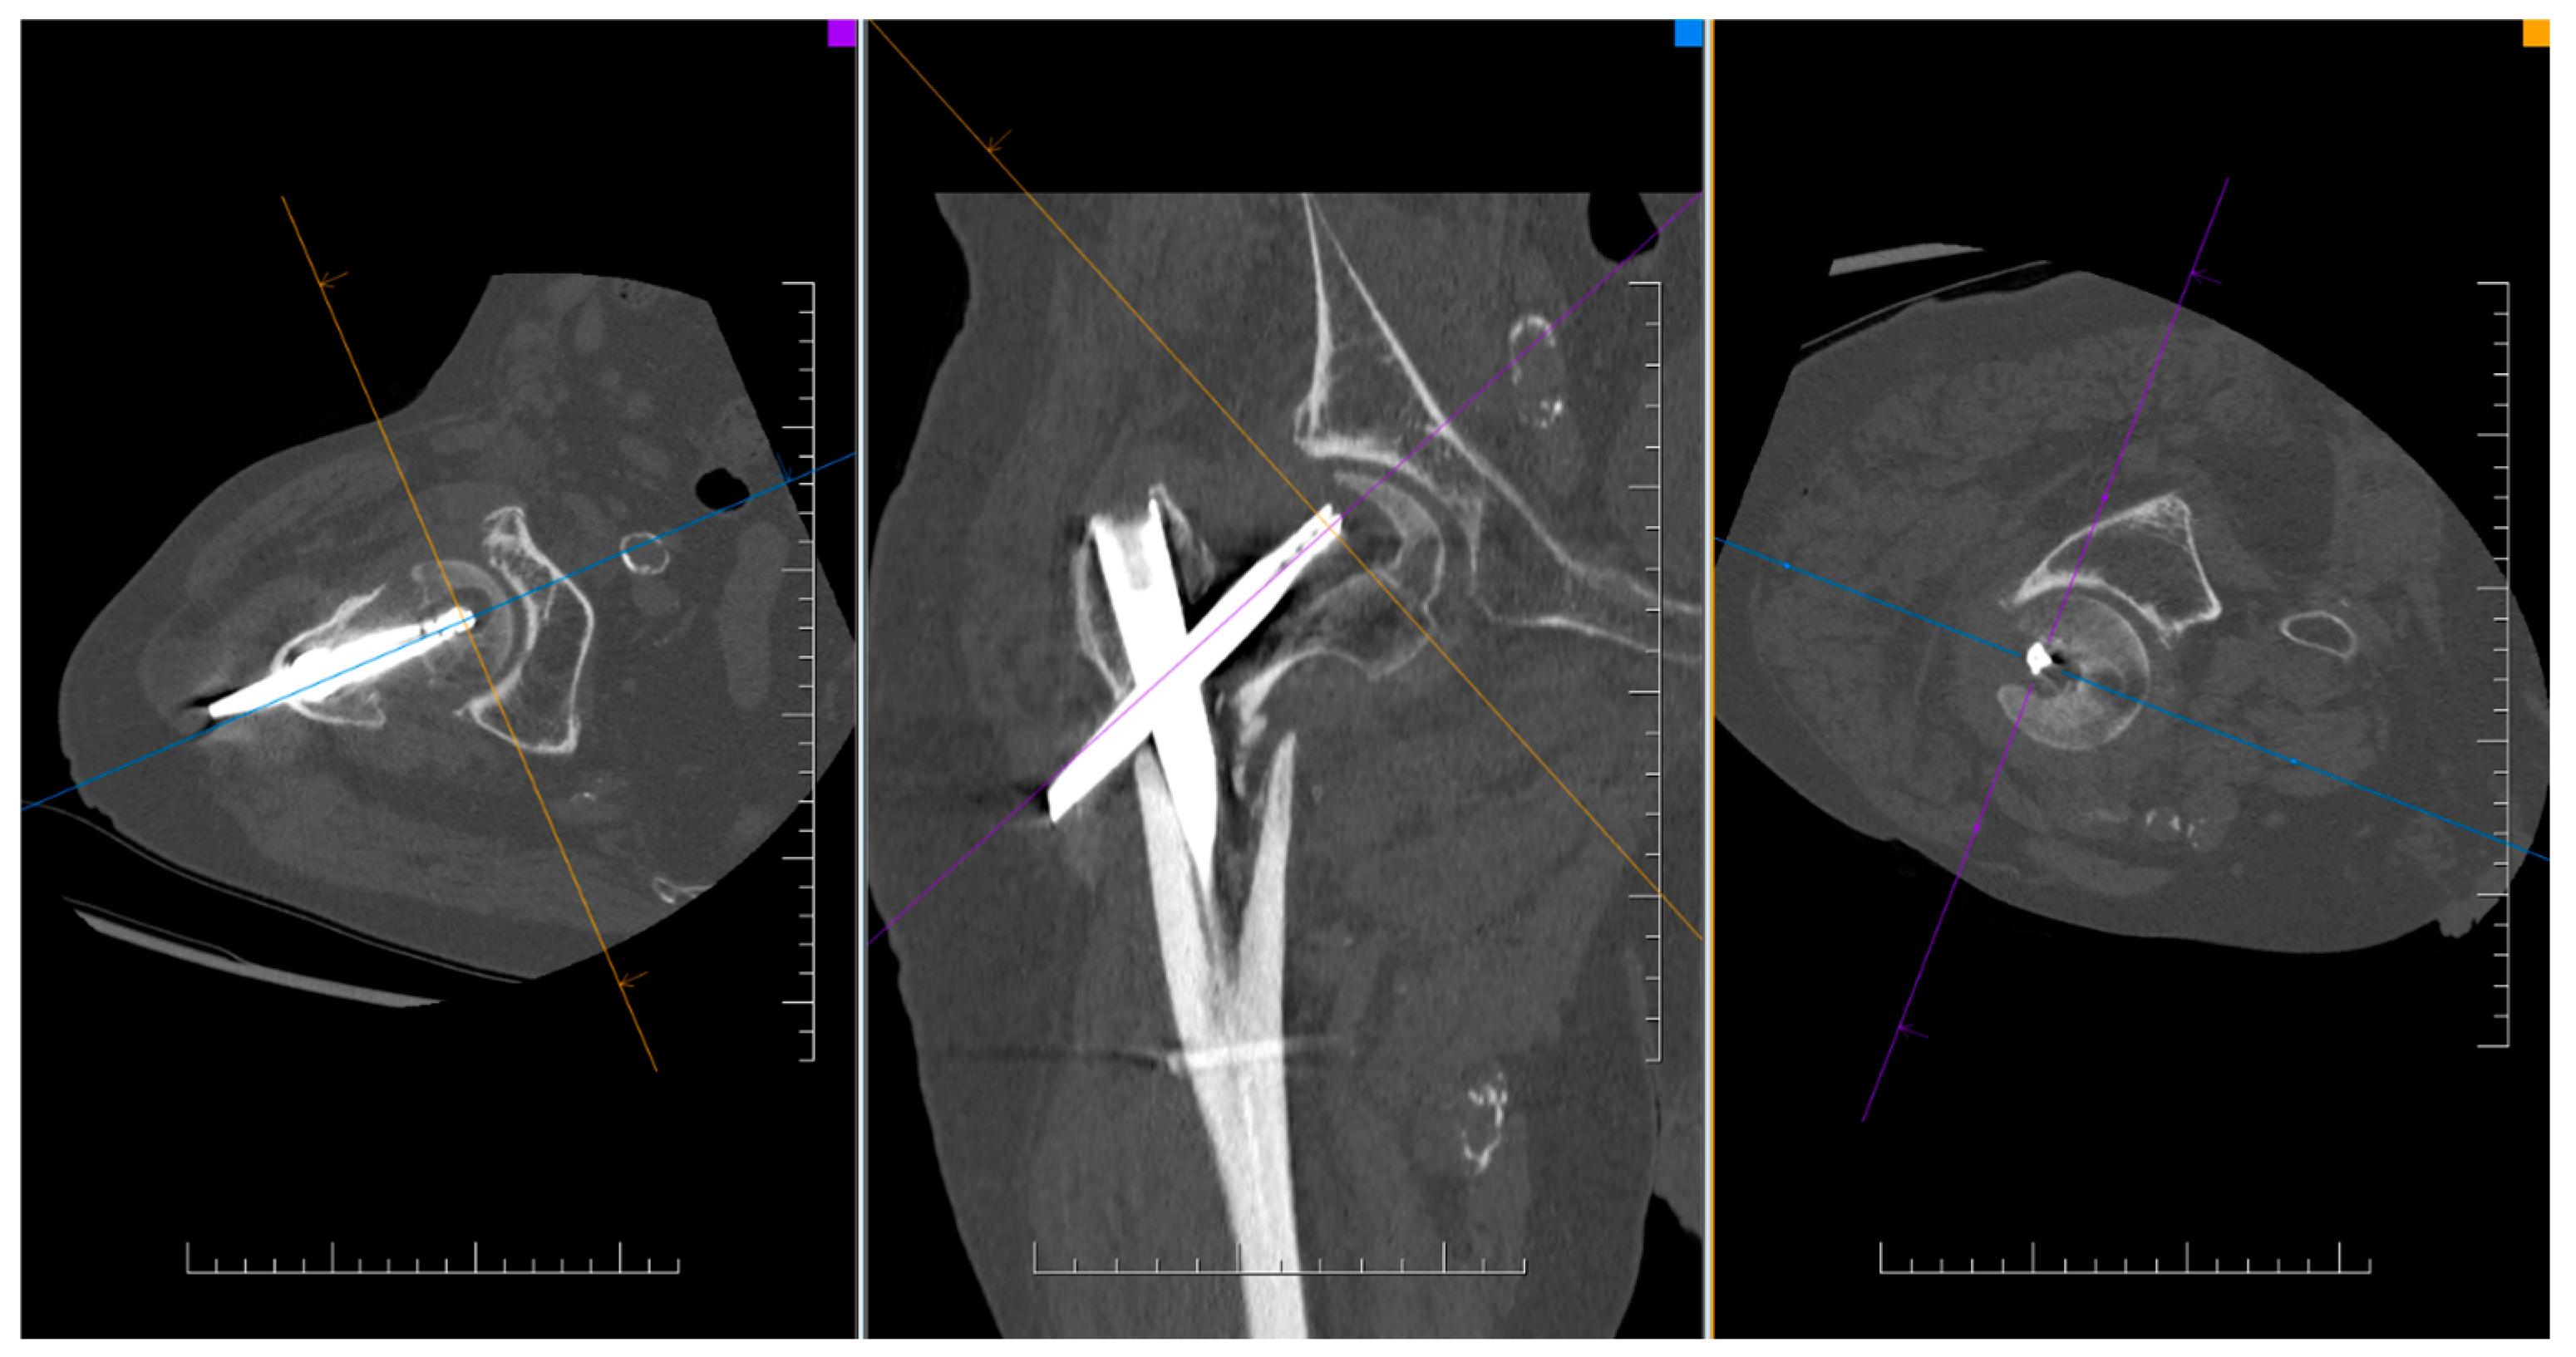

By evaluating the X-ray parameters, eight patients in the cohort in whom postoperative varus deformities of the femoral neck were greater than 10° were founded. Four patients did not have cement augmentation and four had cement augmentation of the nail. In three cases, the blade cut-out and, thus, failure of osteosynthesis was identified. In two women and one man with blade cut-out, a TFN-A implant without cement augmentation was implanted (Figure 3, Figure 4 and Figure 5). In these three cases, the medial cortical line and anterior cortical line were repositioned within 3 mm of dislocation at the anatomical interface. The blade cut-out in the group with cement augmentation was not observed.

Figure 3. CT finding of osteosynthesis failure using TFNA without cement augmentation of the blade and with cut-out.